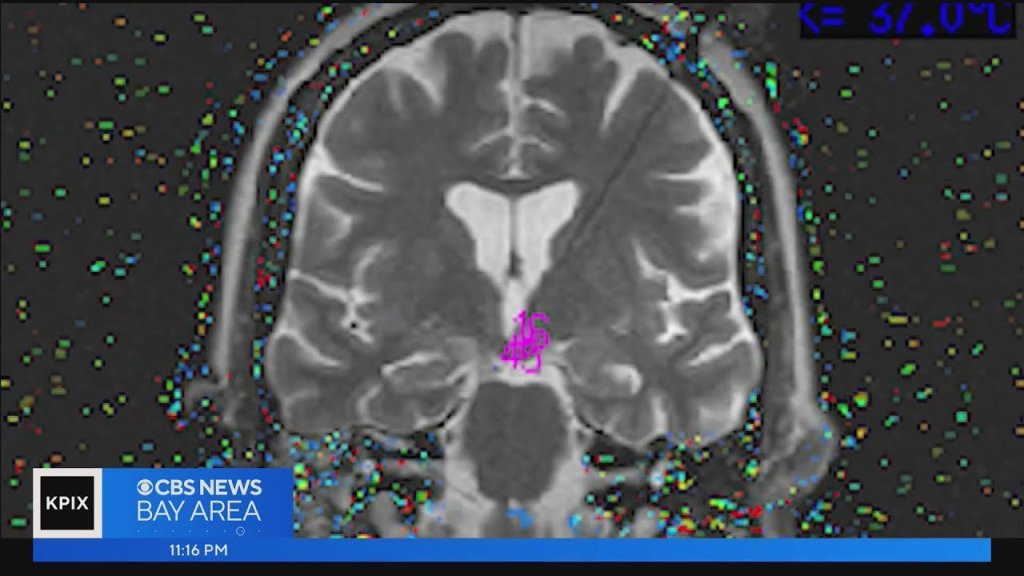

Dr. Paul Garcia, a neurologist who only worked at the hospital a few times a year, was the doctor on call. Upon hearing about Menzies’ behaviors during her seizures, he was intrigued and completed an MRI of her brain. It was there that he spotted a small growth on her hypothalamus the size of a lemon seed. The doctor explained the hypothalamus controls a lot, including the nervous system.